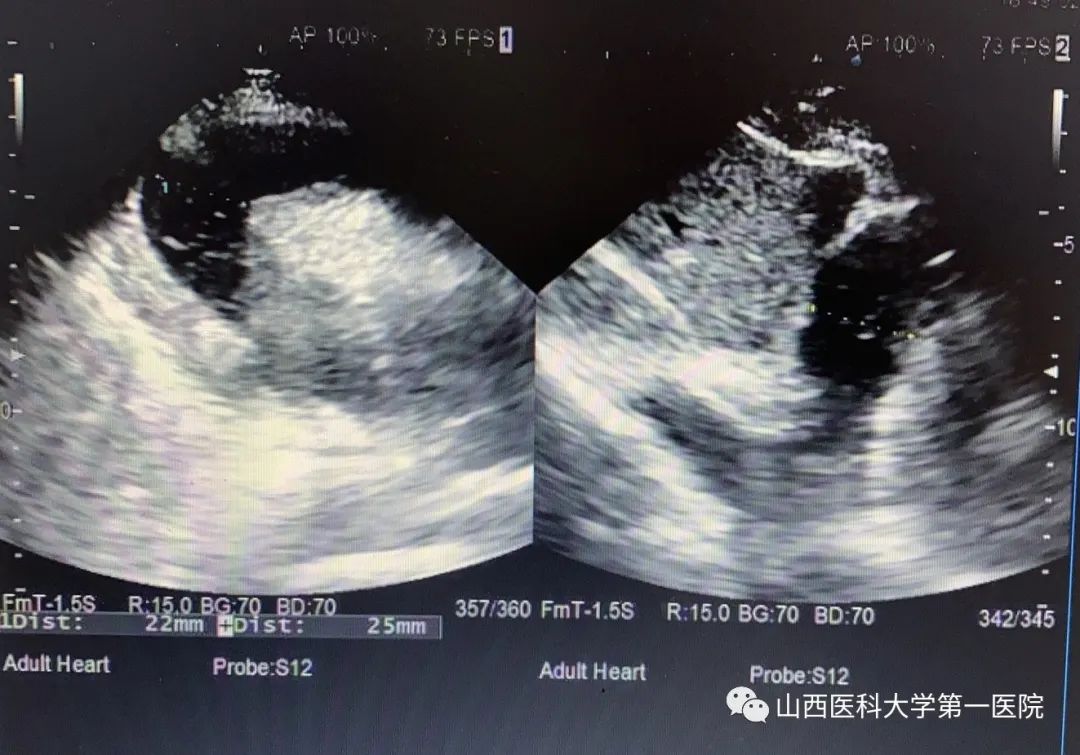

急诊“120”车接回一例车祸外伤患者。该患者自驾车时发生车祸,来院时意识模糊,烦躁明显,不能描述具体受伤过程。经检查,患者面色、口唇青紫,胸部皮肤大面积紫绀,呼吸急促,血氧饱和度46%,呼吸25次/分钟,心率126次/分钟,血压125/100mmHg。急诊科医护团队迅速评估伤情并展开急救:高流量吸氧、建立静脉通路、严密心电监护。患者表现为严重的低氧血症,氧疗后氧饱和度仅上升至60%左右,皮肤仍紫绀,极度烦躁不安。紧急行头、胸、腹、脊柱等部位CT检查。张嘉利医师获得CT影像资料后发现患者存在大量心包积液,结合患者症状,考虑“创伤性心脏损伤致心包填塞”,立即制定心包穿刺术抢救计划,并协调人员与物资。在B超精准定位下,张嘉利医师紧急为患者行床旁心包穿刺置管引流术,术中穿刺抽吸出100ml暗红色血性液。患者低氧血症的症状随即明显减轻,呼吸逐渐平稳,心率逐渐降至正常,血氧饱和度上升至90%以上。后留置引流管持续引流。术后,患者转入急诊ICU密切监护。至11月2日8时,心包穿刺引流管又引流出260ml心包内积血。患者生命体征平稳,对答准确,自诉无明显不适。11月3日,行B超复查后,顺利拔除引流管。